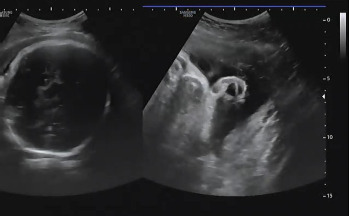

진료 순서가 되어 복부 초음파를 확인하였다. 여전히 햇님이는 자신의 건강함을 알리기 위해 초음파를 보는 내내 손을 이리저리 움직였다. 머리둘레, 복부둘레, 허벅지 뼈 길이를 측정하여 대략적인 체중을 확인하고 태아가 주수에 알맞게 크고 있는지를 확인했다. 머리둘레는 35주 차, 복부둘레는 34주 5일, 허벅지 뼈 길이는 33주 4일이라서 이상하다 생각했는데 평균적 수치는 주수에 알맞게 성장이라는 것을 듣고 안심했다. 2주 뒤인 37주 차에 내원을 예약했다.